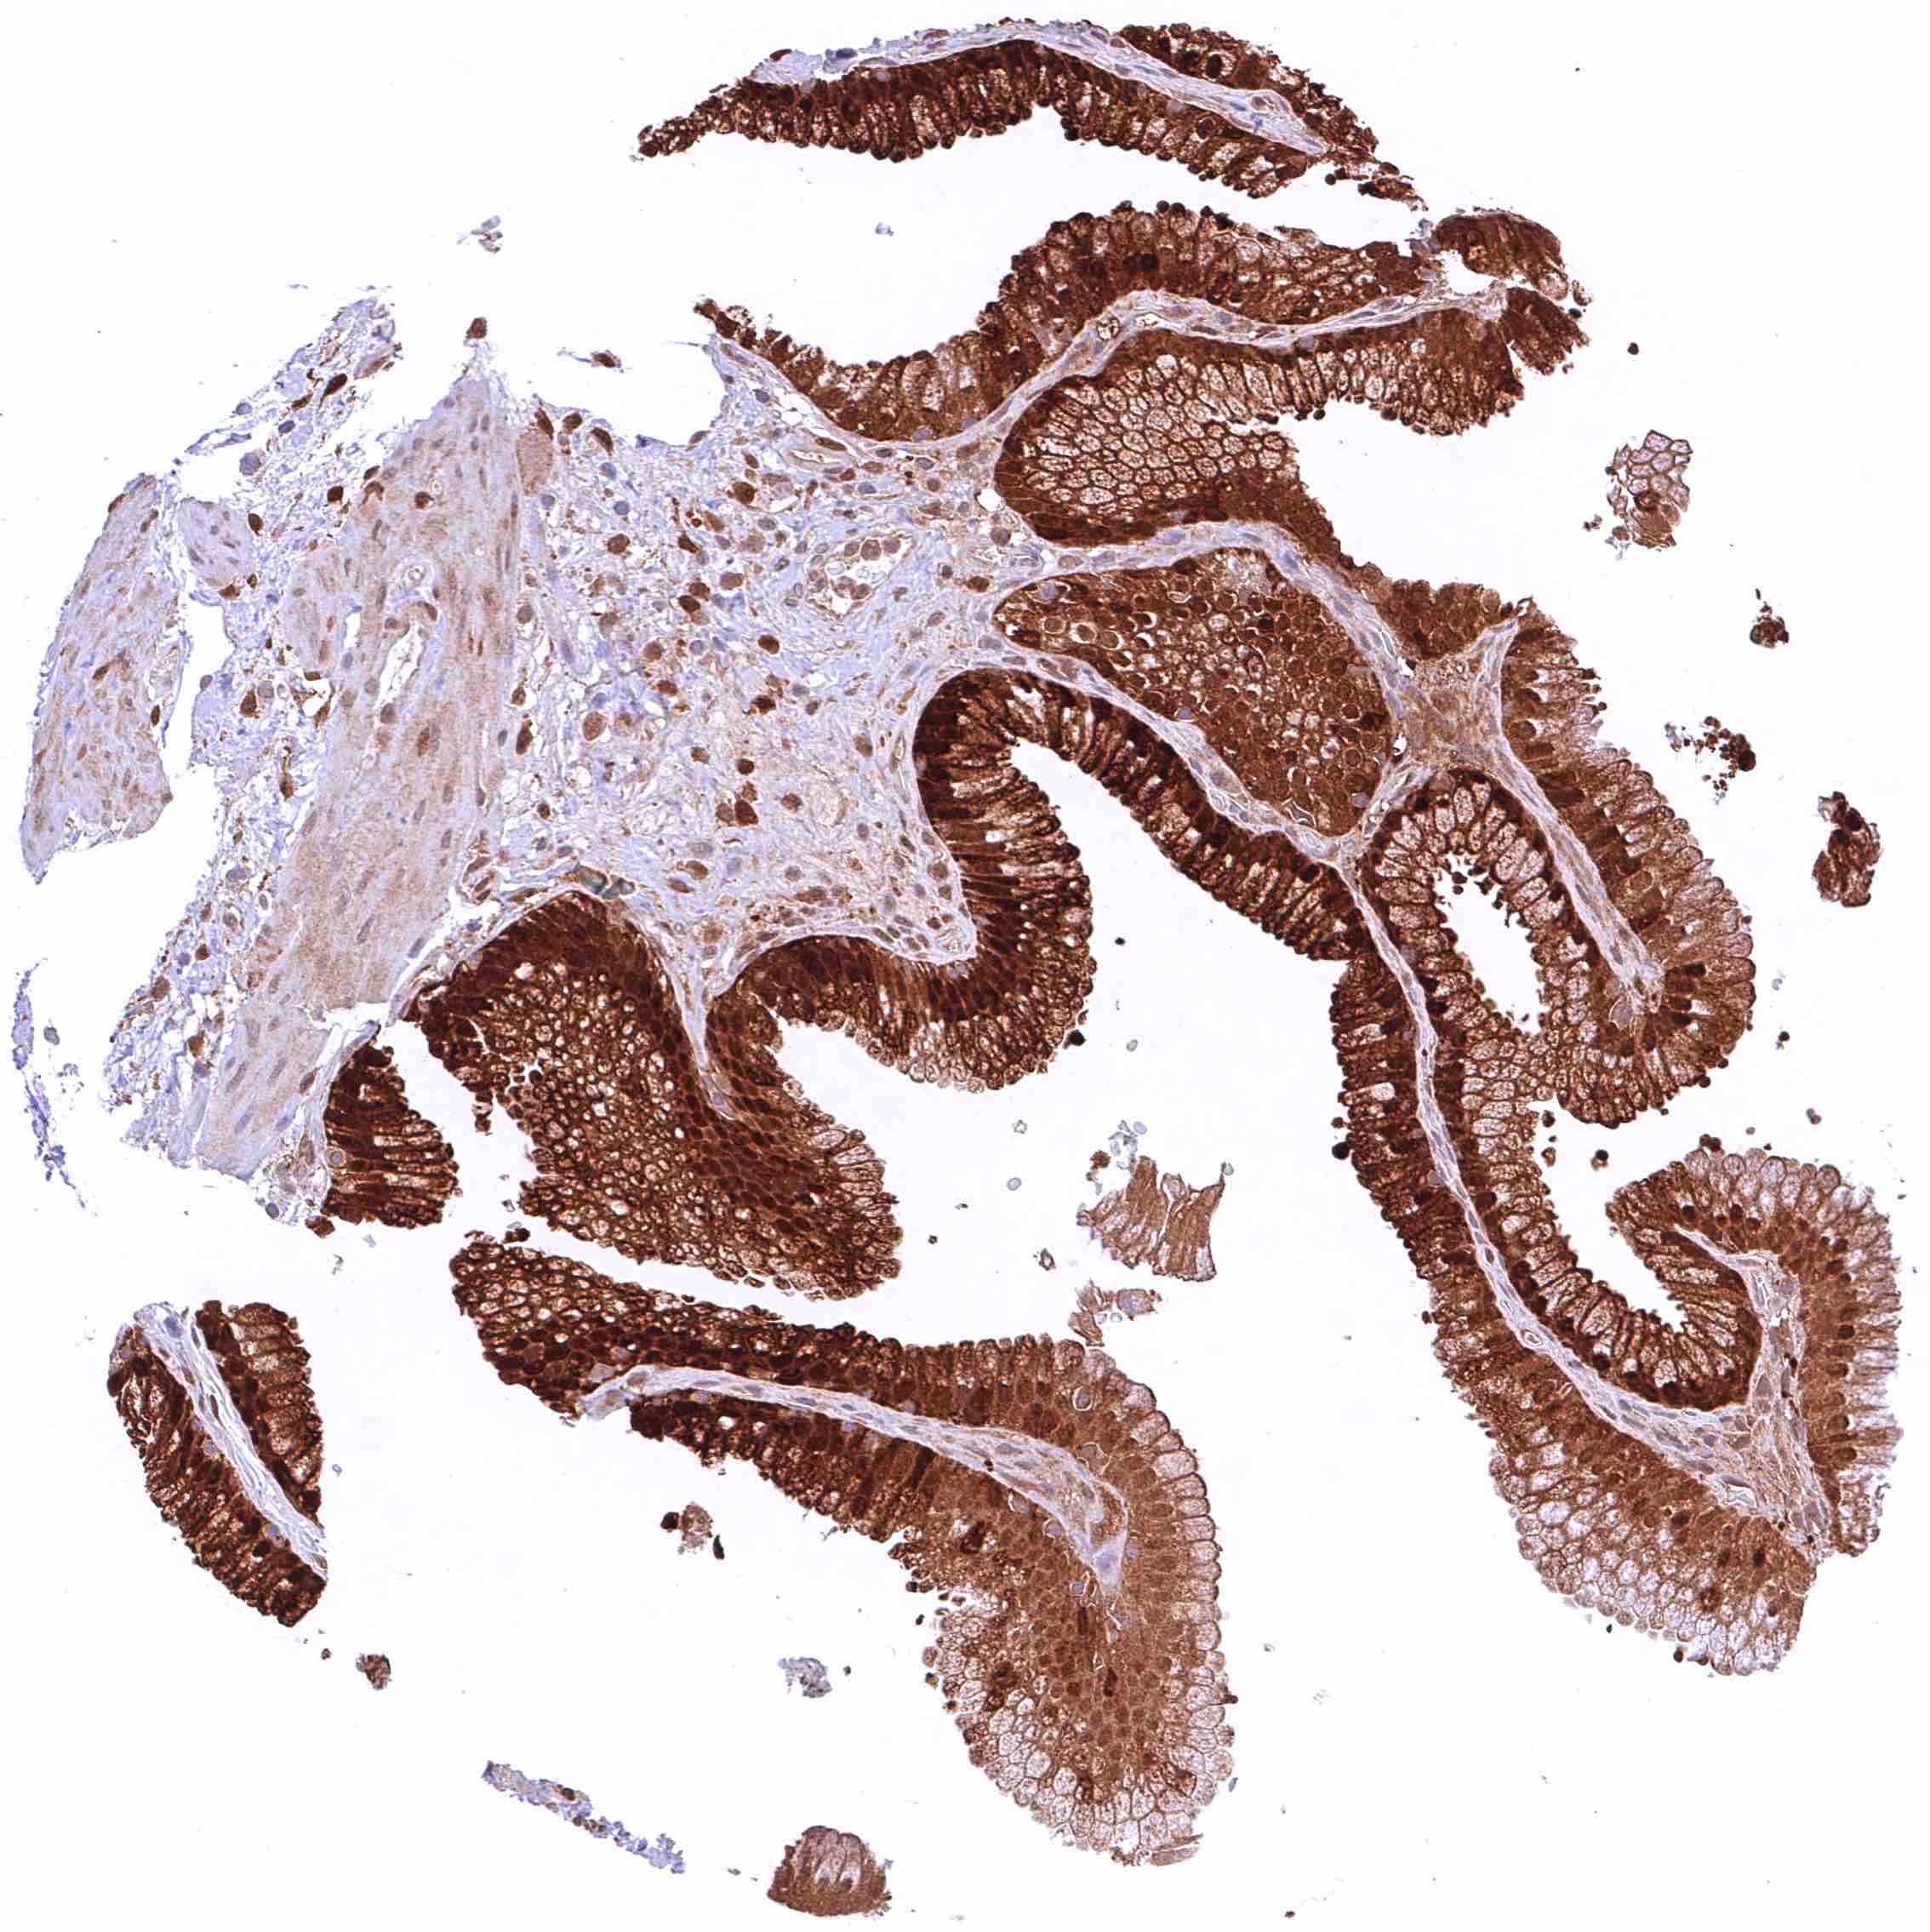

Rectum, mucosa – Strong, predominantly cytoplasmic GSTP1 positivity of epithelial cells. Staining is most intense at the base of crypts and decreases slightly towards the surface epithelium.